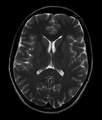

T1 (note CSF is dark) Normal axial T2-weighted MR image of the brain.

Normal axial T2-weighted MR image of the brain.